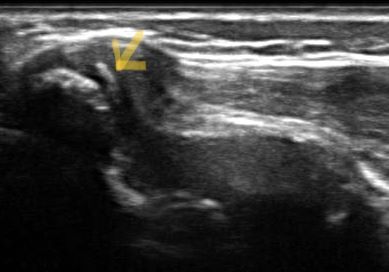

股関節前側の痛みで多いのは、中学生に多い疾患です。大腿直筋の付け根の痛みで、エコー画像では下前腸骨棘(股関節のすぐ下)が骨が乱れて描写されます。陸上、サッカー、ジャンプの多いスポーツなど、大腿部や股関節の使い過ぎで起こります。運動強度を押さえるなどして、施術を受けるとかなり回復します。